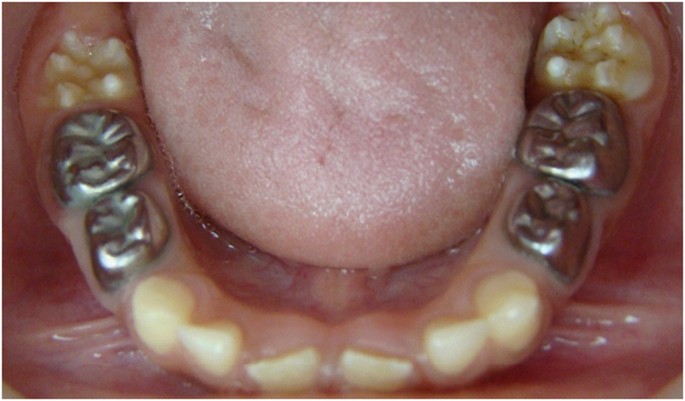

The teeth of this group were received freshly prepared mix of zinc oxide powder and drops of thymus vulgaris ethanolic extract till reaching a paste of suitable consistency (~1: 1 ratio by volume) as a pulp medicament. Then, the pulp chamber was filled with a glass ionomer (Riva, SDI, Bayswater, VIC, Australia) as intermediate restoration. All teeth were restored with stainless steel crowns.

The teeth in the formocresol group had a clinical success rate of 100% at 1 month, 94.4% at 6 months and 88.2% at 12 months (Figures 2,3,4,5,6,7,8). The teeth in the propolis group had a clinical success rate of 94.7% at 1 month, and 88.2% at 6 and 12 months. The thymus vulgaris group had a clinical success rate of 94.4% at 1 month, and 94.1% at 6 months and 12 months follow-up. Statistical analysis of the data, using Friedman’s test, revealed no statistically significant differences between the three groups at all follow-up appointments (Table 1).

The teeth in the formocresol group had a radiographic success rate of 95.0% at 1 month, 81.2 at 6 months and 73.3% at 12 months. The teeth in the propolis group had a radiographic success rate of 94.7% at 1 month, 81.2% at 6 months and 73.3% at 12 months. The thymus vulgaris group had a radiographic success rate of 94.4% at 1 month, and 87.5% at 6 and 12 months. Statistical analysis of the data, using Friedman’s test, revealed no statistically significant differences between the three groups at all follow-up appointments (Table 2).